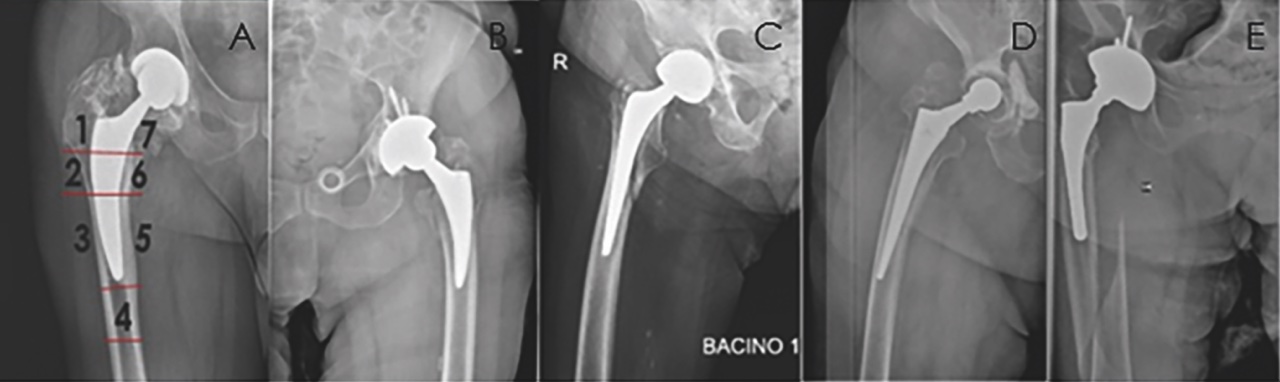

L’imaging può permettere di valutare lo stato di salute delle componenti protesiche; esami di primo livello sono le radiografie di bacino e anca, da comparare con immagini precedenti per rilevare eventuali campanelli di allarme per una possibile mobilizzazione asettica. Per la valutazione dello “stato di salute” dello stelo femorale viene effettuata un’analisi delle sette zone di Gruen (Fig. 1), per indicare in modo univoco aree di scollamento, strie di radiolucenza, stress shielding, effetto mensola, cedimenti dell’impianto, subsidenza, frattura periprotesica, osteolisi, etc. Approfondimenti diagnostici possono essere eseguiti con tecniche di secondo livello come la TAC per valutare il bone stock e il posizionamento delle componenti, la RM per valutare la compromissione o il coinvolgimento dei tessuti molli periprotesici, e la Scintigrafia o la PET per escludere una infezione periprotesica.

Vi sono diverse classificazioni che vengono utilizzate per identificare le fratture periprotesiche dello stelo, tra le più famose ricordiamo la classificazione di Duncan & Masri-Vancouver 5, che suddivide le fratture in base alla posizione, stabilità dello stelo e bone stock (Fig. 1).